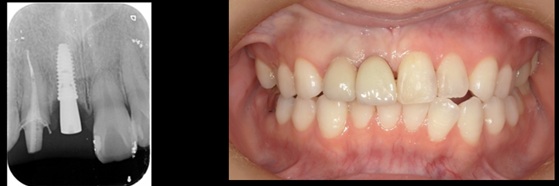

インプラント

抜歯即時フラップなしで埋入し3か月後に完成

治療前

治療後

施術名 | 抜歯即時インプラント埋入 |

主訴 | 前歯が痛い。破折していました |

施術の副作用(リスク) | 感染脱落 |

施術の価格 | 1本GBR5万~10万(税抜き)+インプラント埋入補綴まで35万(税抜き) FGG5万 ソケットリフト6万 |

コメント | 前歯2本抜歯即時で歯茎も切らずに埋入をして3か月後に補綴を行いました右上歯ソケットリフトで対応しました |